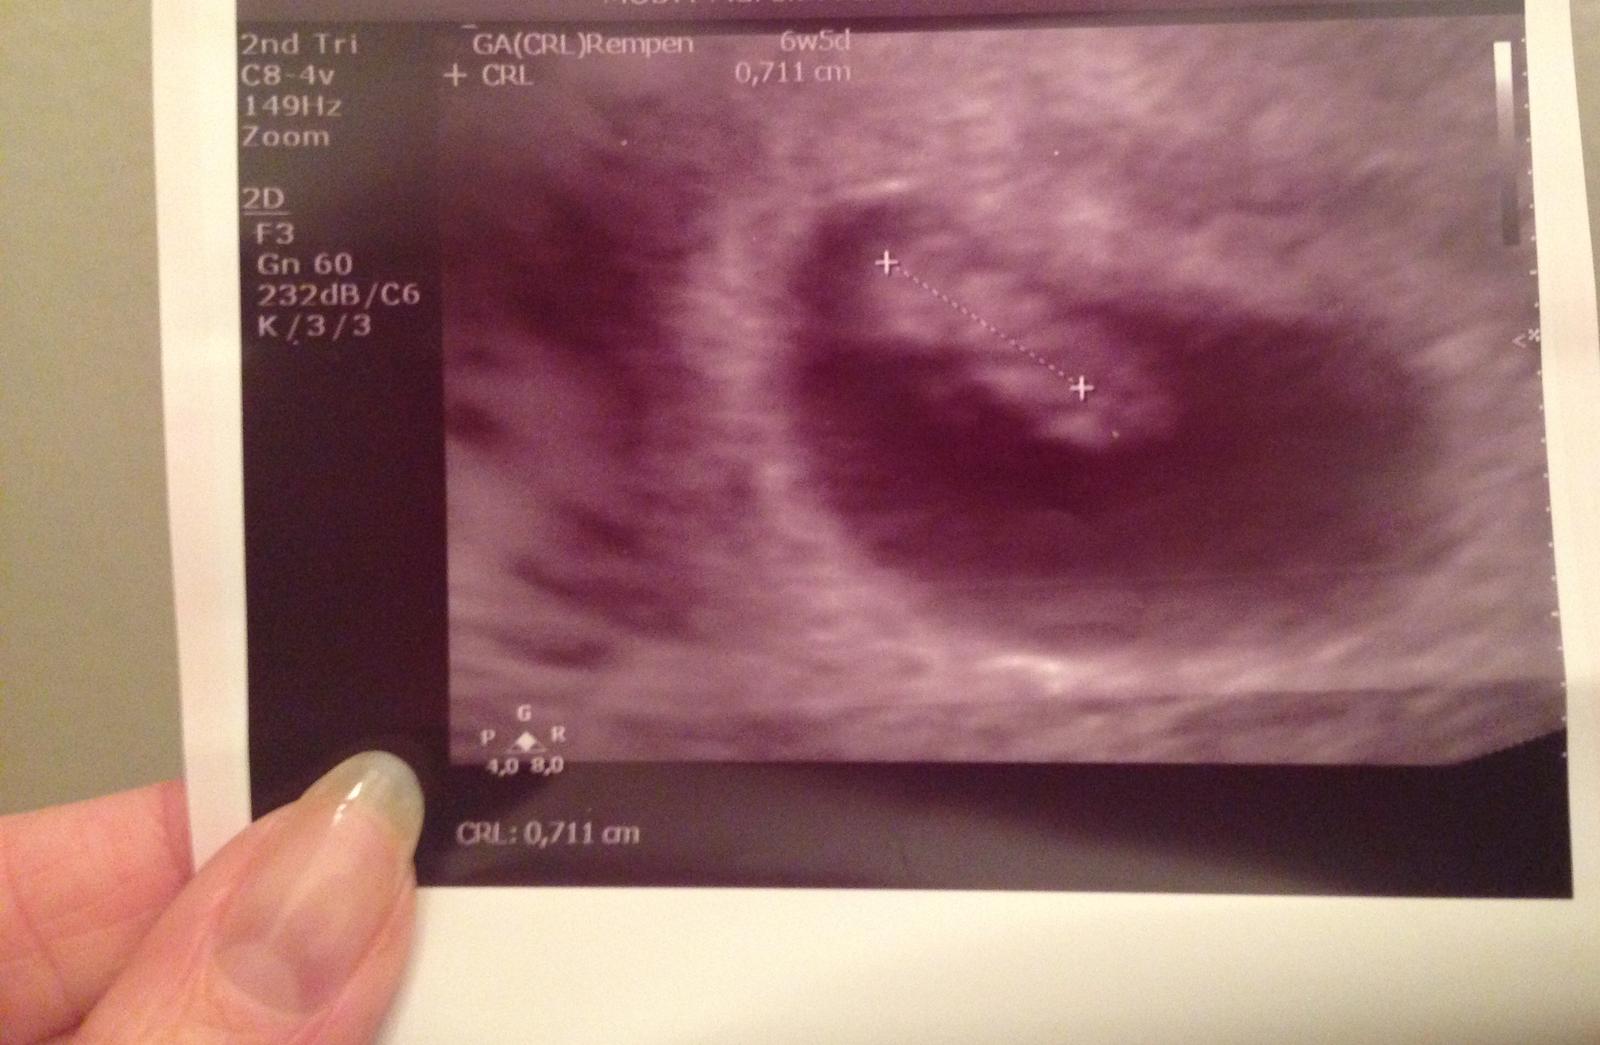

Ahojte..tak moje prvé sono dnes dopadlo tak že..som 6 tt+ 5 a mame 8 mm 🙂 pevne verim,ze kazda z nas to tu dobojujeme az do konca 👣🍼